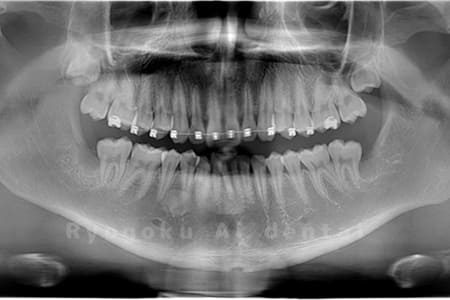

Case02

-

- 原因

- 下顎の水平埋伏智歯

- 治療内容

- 下顎の水平埋伏智歯を抜歯

<リスク・副作用>

手術後は痛み、腫れ、痺れなどの副作用が生じる場合があります。